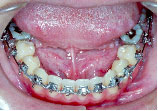

術前矯正が終わりました。一見きれいになったようですが下あごはまだ左にずれたままです。

手術を担当する口腔外科医と最終打ち合わせをします。

手術時には必ずレントゲン上での計画(ペーパーサージェリー)と模型上でより具体的な計画を立てます。(モデルサージェリー)

上あごは左へ2mm,前方へ2mm(Le Fort 1型)、下あごは右後方へ3.5mm,正面右へ3mm、左後方へ2.5mm(IVRO)、また顔のバランスをとるためあごの先を前方に5mm移動しました。(genioplasty)手術が終わり、退院当日にできるだけ来院していただきます。この方は手術後13日目でした。

手術前に製作して渡しておいた装置(オルソサージカルスプリント)を入れ、ゴムをかけた状態できていただきます。